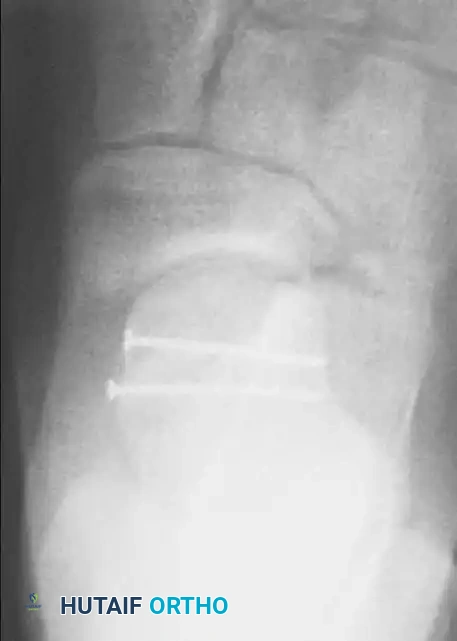

Step-by-Step Operative Technique (ORIF)

1. Joint Inspection and Debridement: The fracture hematoma is evacuated. Small, avascular, non-articular osteochondral fragments that cannot be fixed are excised.

2. Reduction of Impacted Fractures: If the articular surface is impacted, a small osteotome or dental pick is used to carefully elevate the articular fragment to match the contour of the navicular.

3. Bone Grafting: Once elevated, a void is inevitably created behind the articular fragment. This must be filled with cancellous bone graft (autograft from the distal tibia or calcaneus, or allograft) to provide subchondral support and minimize postoperative collapse.

4. Reduction of Shear Fractures: Large shear fragments are reduced anatomically using pointed reduction forceps.

5. Fixation: Stable fixation is accomplished using 2.0 mm to 3.0 mm partially threaded cancellous lag screws, headless compression screws, or bioabsorbable pins. Fixation can be placed directly through the dorsal incision or percutaneously from the medial side as dictated by the fracture geometry. All screw heads must be countersunk beneath the articular cartilage to prevent impingement on the navicular.

6. Joint Stability Assessment: Care must be taken to ensure the talonavicular joint is concentrically reduced. If the joint remains unstable after fracture fixation, it may be necessary to place a temporary Kirschner wire (K-wire) across the talonavicular joint to hold it reduced.

7. Medial Column Restoration: In cases of fracture-dislocation with shortening of the medial column, an intraoperative external fixator (spanning from the medial cuneiform to the medial talar body or calcaneus) may be required to distract the joint, gain length, and facilitate reduction.

Image